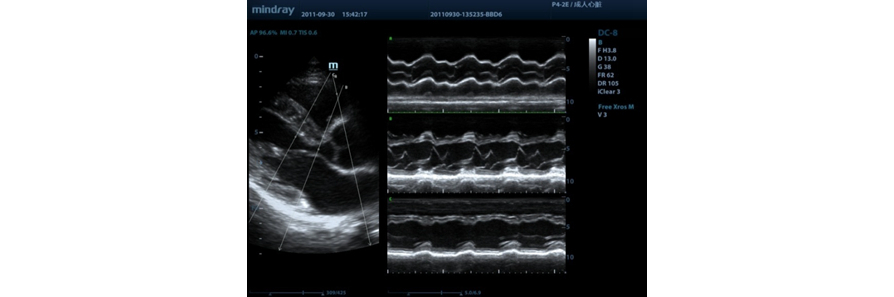

Free Xros M?

Osservazione anatomica precisa posizionando liberamente le linee campione su ciascun angolo. Migliori immagini con visualizzazione simultanea fino a 3 linee campione.